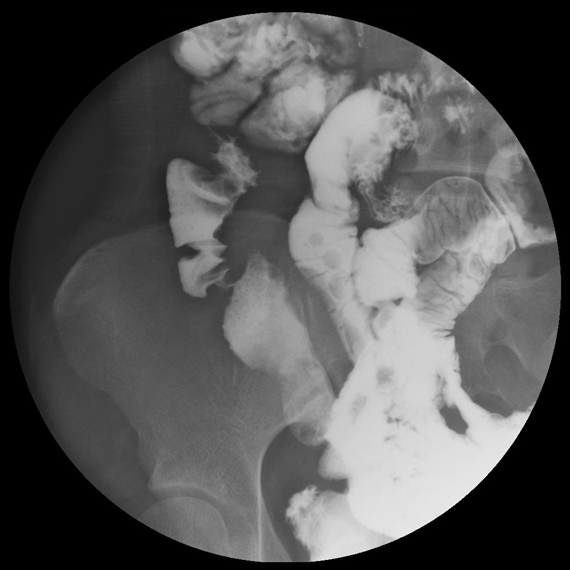

MRエンテログラフィー 3

腸管腸管ろう(小腸造影検査との比較)を認める。

出典

img

1: 難治性炎症性腸管障害に関する調査研究(久松班):一目でわかるIBD 炎症性腸疾患を診察されている先生方へ(第四版) 「令和4年度において、厚生労働科学研究費補助(難治性疾患等政策研究事業(難治性疾患政策研究事業)を受け、実施した研究の成果」、2023年、P29